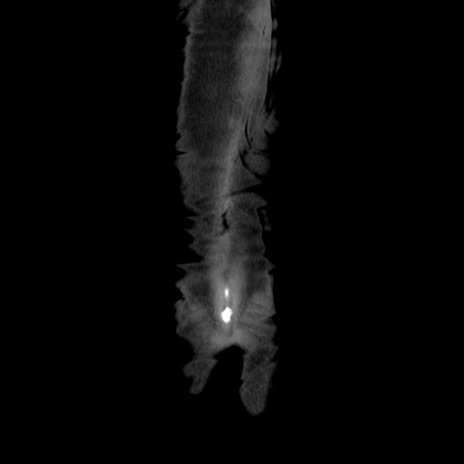

症例37(冠状断像)

横断像